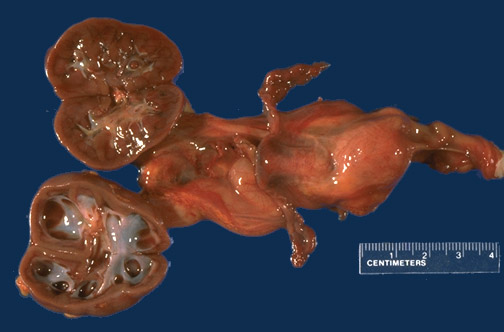

A right ureteral obstruction in this case led to right hydronephrosis. Though obstruction can lead to cortical microcyst formation, these microcysts are typically not grossly visible.